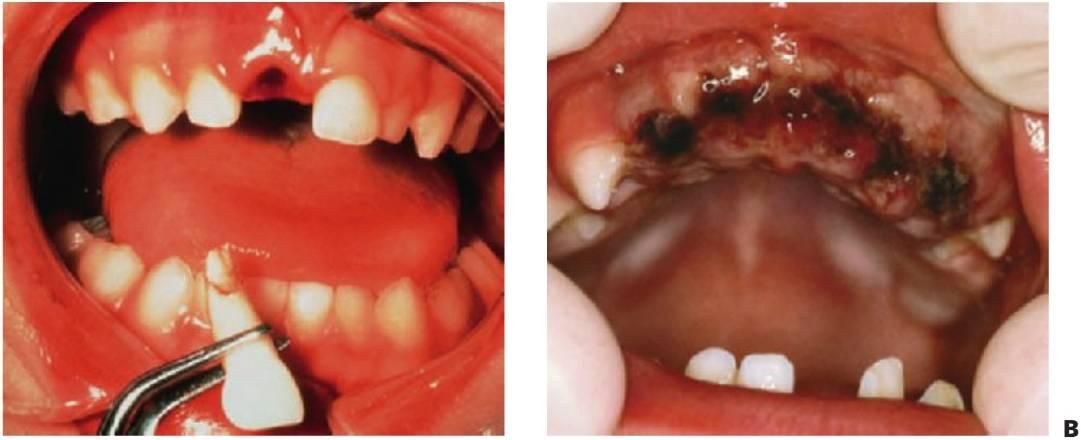

La región orofacial sufre la mayor afectación de traumatismos durante los episodios de maltrato infantil (fig. 7.2) y estos traumatismos no accidentales tienen como resultado diferentes tipos de lesiones, como las lesiones que no concuerdan con el relato ofrecido, los hematomas en tejido blando que no cubren prominencias óseas, las lesiones que adquieren la forma de un objeto reconocible o la multitud de lesiones que aparecen en el mismo niño a diferentes edades; asimismo, las marcas de mordeduras en niños se consideran maltrato infantil hasta que se prue be lo contrario. Para establecer la adecuada notificación, tratamiento y prevención de más lesiones, deben ser del total conocimiento del especialista tanto las características y las conclusiones del diagnóstico de maltrato infantil como el protocolo para denunciar tales hechos.

La exploración debe llevarse a cabo siguiendo un orden lógico. Resulta importante examinar todo el cuerpo, pues el paciente podría presentarse en primer lugar en la consulta del especialista dental pero haber sufrido otro tipo de lesiones (fig. 7.3 y v. cap. 1).